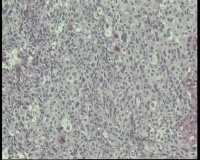

性别年龄68岁临床诊断宫内容物,性质待病理

一般病史停经10余年

标本名称宫内容物

大体所见粉白色块状组织1.0x0.8x0.6厘米—1.9x1.0x0.5厘米4块

怎么显示非法数据不让发送。患者女68岁,停经10余年,不规则阴道流血2个月,阴道自行排出物送病理,镜下未见子宫内膜腺体,子宫内膜间质样细胞异型明显,核分裂多见,是高度高度恶性子宫内膜间质肉瘤吗?

象分化差的内膜癌,这个要做IHC与相关恶性肿瘤鉴别……

恶性肿瘤,鳞癌或腺癌,还是子宫内膜间质肉瘤,建议IHC标记明确。

恶性肿瘤;建议:HMB-45;Melan-A;SMA等‘排除PEComa(恶性)的可能性。

鳞状细胞癌,建议检查宫颈,排除是原发还是转移